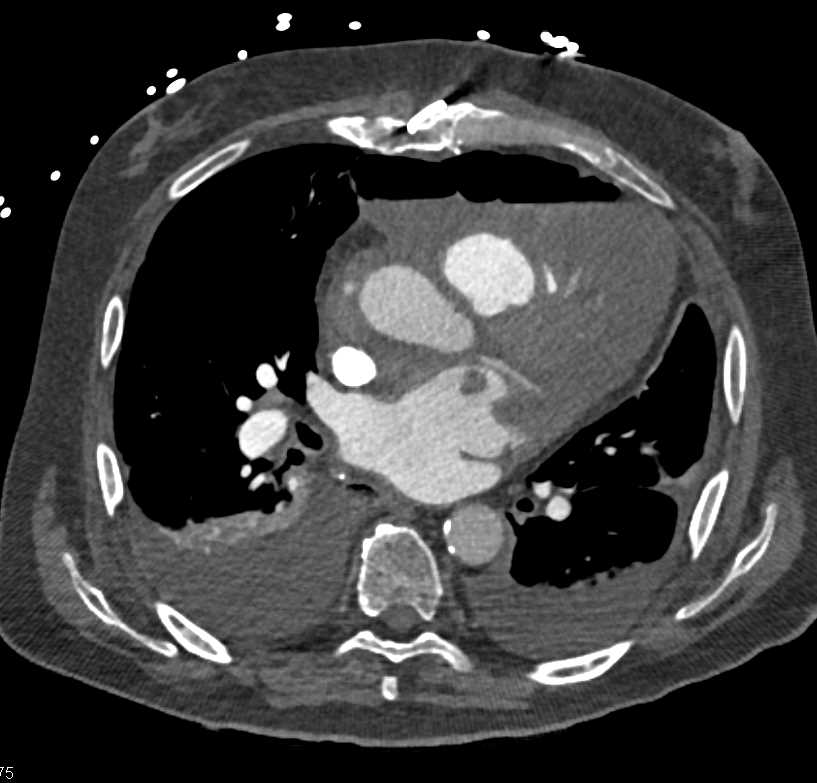

CT appearances and findings are the primary objective for radiologists to determine the accurate diagnosis during reading scans while considering patients' clinical presentation.

This section provides CT appearance for major organ systems and their common malignancies for the radiologists' convenient access that are supplemented with related pearls and lectures from CTisus to enhance radiologists' knowledge for each pathology.

Deep Learning - Deep Learning and Cardiothoracic Apps

View moreAccess over 322,000 CT Scans and the diagnosis that is identified for each case. The case studies range from CT Scans, MRI, and X-Rays, and are organized by anatomical region: Cardiac, Pancreas, Pediatric, Vascular, Gastrointestinal and more.